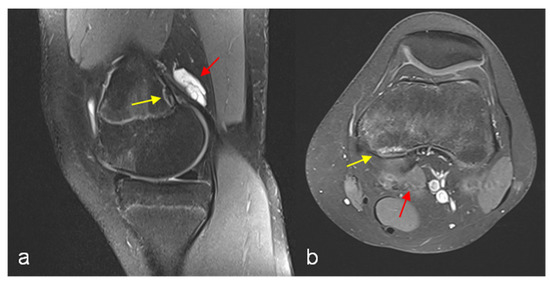

The finding of DFCI was defined as a circumscribed, usually oval area of high signal intensity expanding into bone on fat-suppressed proton density or T2-weighted MRI scans, usually with a thin dark rim at the periphery representing sclerosis [2]. The presence of an accompanying paratendinous cystic lesion is optional (Figure 1).

Figure 1. MRI left knee PD TSE FS sagittal reconstruction (a) and T1 TSE FS (Gd contrast agent) transversal reconstruction (b). Cystic fluid-filled lesion above the femoral origin of the medial gastrocnemius head with marginal Gd enhancement (red arrows), discrete signal enhancement at the tendinous insertion site. Cortical irregularity (DFCI) with signal enhancement and low-signal marginal sclerosis (yellow arrows).